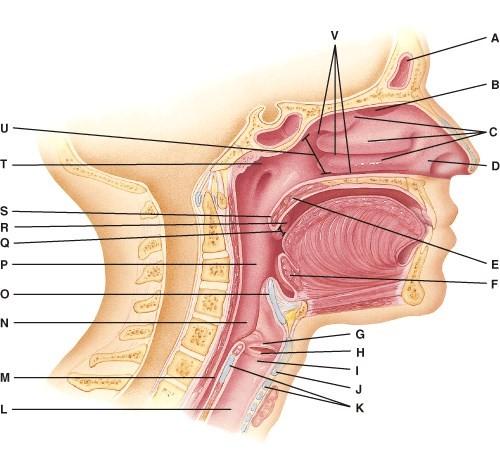

Where are the nasal conchae?

- A

- C

- T

- U

- V

B

This portion of the pharynx has five openings in its wall.

- C

- E

- N

- P

- T

E

Which tonsils are found in the oropharynx?

- V

- R

- S

- Q

- U

B

What is also referred to as the Adam’s Apple?

- G

- H

- I

- J

- K

D

Where is the larynx?

- I

- M

- L

- N

- O

A

This is a ring of hyaline cartilage that forms the inferior wall of the larynx.

- J

- K

- G

- H

- O

B

Where is the uvula?

- E

- F

- Q

- S

- U

D

Where are the palatine tonsils?

- E

- F

- R

- U

- None of the above

C

Where is the soft palate?

- C

- E

- G

- Q

- S

B

Where is the epiglottis?

- O

- R

- S

- F

- Q

A